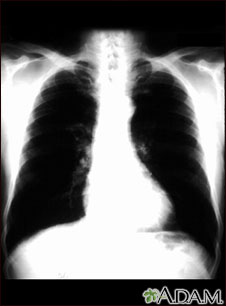

Bronchial cancer - chest x-ray

This is a chest x-ray of a person with bronchial cancer. This is a front view. The lungs are the two dark areas. The heart and other structures are white areas visible in the middle of the chest. The light areas that appear as subtle branches extending from the center into the lungs are cancerous.